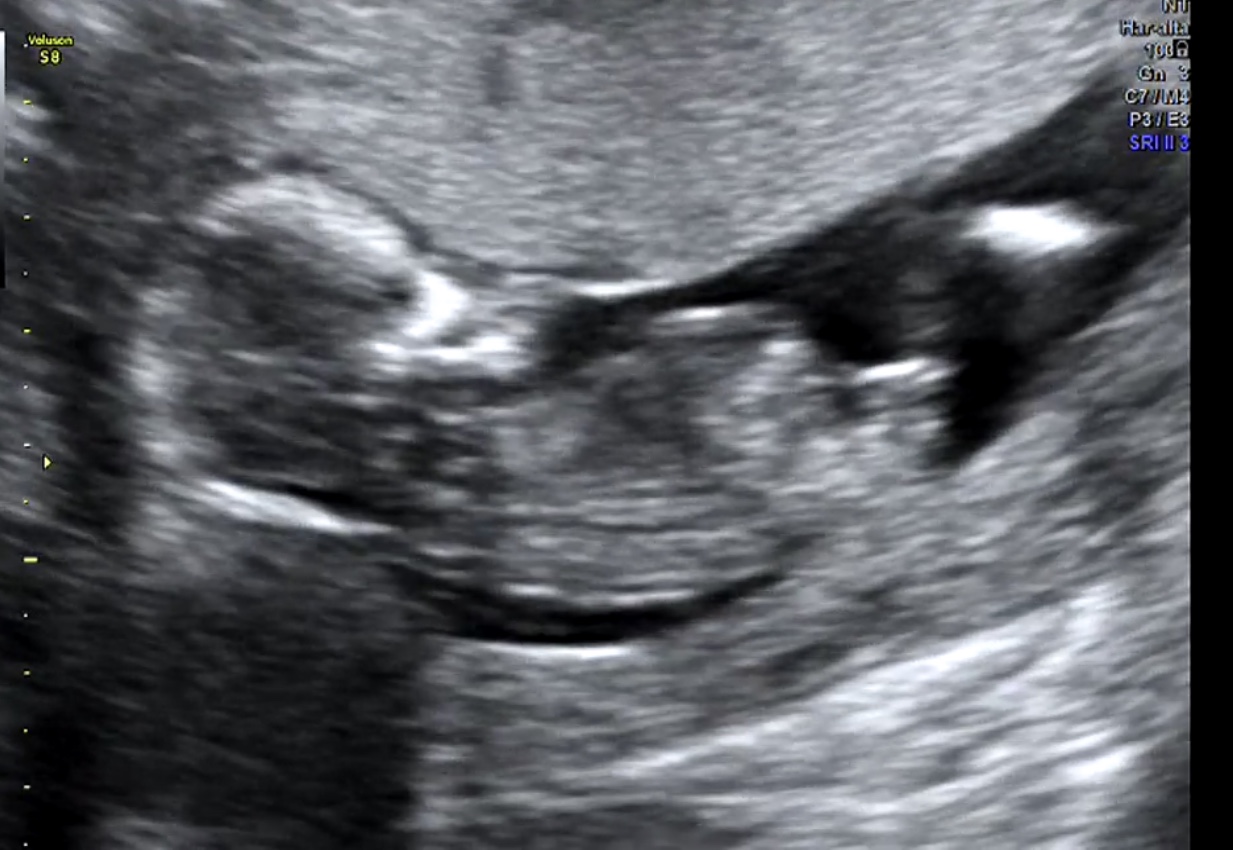

I am so anxious here! We went to the doctor yesterday for my 13 week scan and the doctor said he knew the grnder, but my husband doesn’t want to knooow! (So frustrating) we have 2 boys and want to know if I need to buy things or recycle!!

I will appreciate your help!!Attachment 40938Attachment 40939Attachment 40940